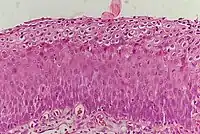

_normal_squamous_epithelium.jpg)

La NCI est classée en grades[14] :

| Grade histologique | Cytologie correspondante | Description | Image |

|---|---|---|---|

| 1 (catégorie I) | Lésion malpighienne intra-épithéliale de bas grade (LSIL) |

|

| 2/3 | Lésion malpighienne intra-épithéliale de haut grade (HSIL). |

| |

| 2 (grade II) |

| ![]() | |

| 3 (grade III) |

| ![]() |